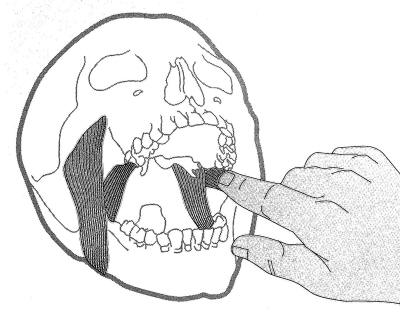

Palpación del haz inferior del pterigoideo externo: |

Para palpar el haz inferior del pterigoideo

externo, se realiza con el dedo meñique y se lo ubica por

delante del pilar anterior hasta la zona de tuberosidad. En

ese momento se desliza el dedo hacia atrás, con presión

moderada. El paciente puede sentir una molestia moderada,

hasta un dolor exquisito.

Si existe dolor intenso a la

palpación es señal de que el paciente presenta bruxismo. |